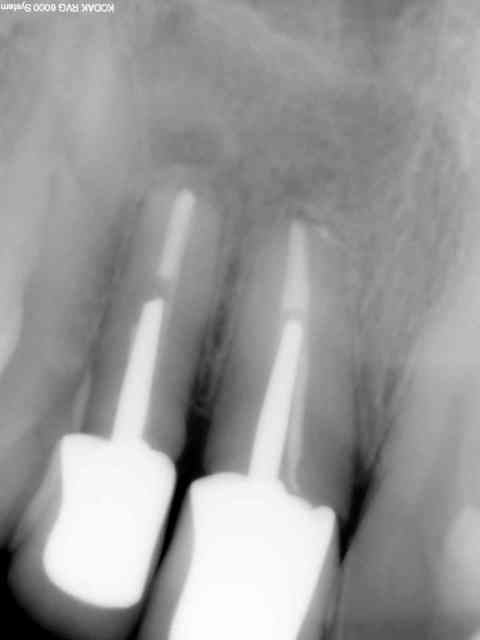

patiente porteuse de ccm sur 12 11 ayant subi une resec sans reprise de tr simultanée me consultant pour une "petite voussure" vestibulaire.

resec obturation endo simultanée

le résultat à 1 an et à 7 ans

en fait je parlais d'utilisation d'un matériau de comblement osseux susceptible de'être ostéoinducteur ou ostéoonducteur, la reconstruction osseuse dans ce cas est assez flagrante surtout qu'à l'élévation du lambeau il n'y avait plus aucune corticale vetibulaire et la corticale palatine était plus qu'en voie de résorbtion ce que l'on voit à la rétro, en revanche il est vrai que l'irm pour l'obturation à rétro peut donner de bons résultats mais dans ce cas je ne l'ai pas pratiqué endo et resection simple.

dans ce cas comme dans la plupart des cas de resec franchement le meilleur matériau biocompatible : RIEN , la meilleure membrane je vous laisse deviner ....